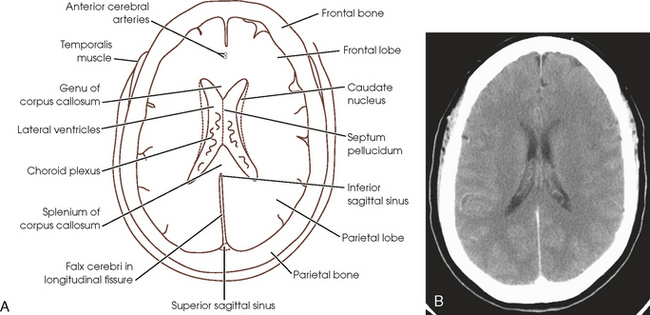

Sectional Anatomy For Radiographers Radiology Key

Sectional Anatomy For Radiographers Radiology Key

Sectional Anatomy For Radiographers Radiology Key

Sectional Anatomy For Radiographers Radiology Key

Sectional Anatomy For Radiographers Radiology Key

Sectional Anatomy For Radiographers Radiology Key